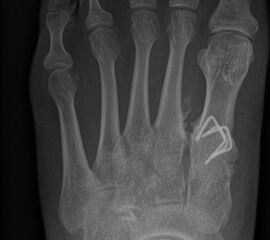

Zehenfehlstellungen

Im Rahmen von sub- oder superduktischen Zehen oder bei Vorhandensein einer Kirner-Deformität werden in unserem Team Kleinzehenkorrekturen entweder komplett oder inkomplett und sowohl am Grundglied kombiniert als auch am Mittelglied durchgeführt (Abb. 20).

Werden komplette Osteotomien an den Zehen durchgeführt, fädeln wir die Osteotomien mit einem 1.2 oder 1.4 mm Kirschner-Draht auf, damit die einzelnen Fragmente nicht verkippen (Abb. 22).

Abb. 22 a-d: Präoperative Klauenzehen beim Jugendlichen in zwei Ansichten (a-b) und postoperative Auffädelung mit Kirschner-Drähten linker und rechter Fuß (c-d).